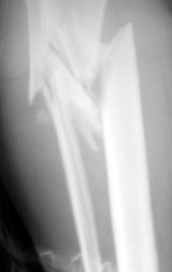

Рентгенограмма при поступлении. Думаю на ней видно распространение линии перелома вниз

На снимке не видно, как далеко по диафизу идет линия перелома. На мой взгляд, лучше сделать еще один снимок, как бы не пришлось делать АВФ из 4

опор.